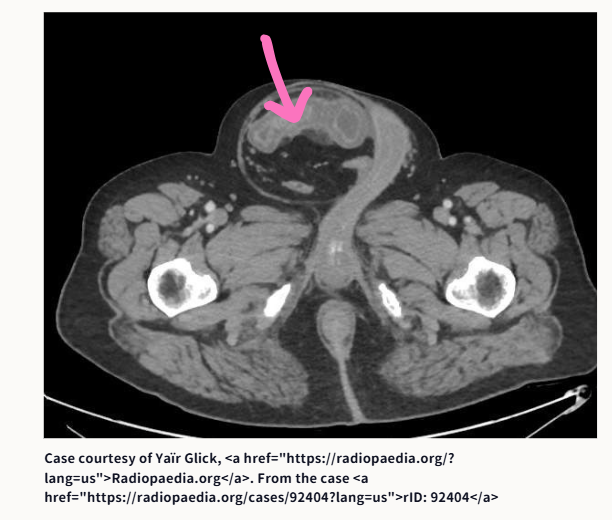

①腸閉塞です。原因は何でしょうか?

①腸閉塞の原因は、鼠径ヘルニア嵌頓でした

こあら先生が提示したCT画像は、以下のサイトからのものです。ピンクの矢印は、こあら先生が書き込んだものです。